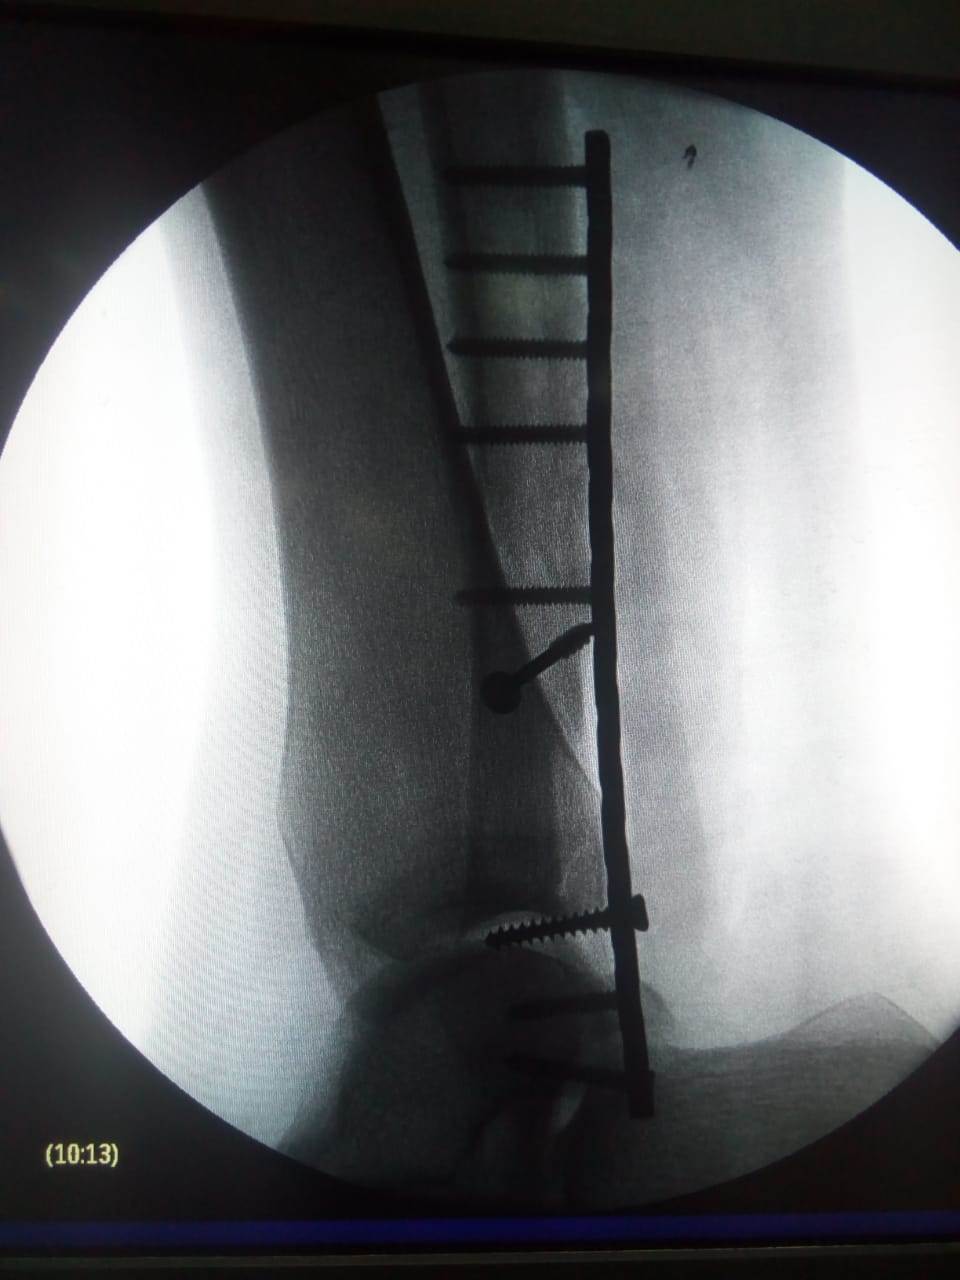

وأضاف د. أحمد عبد العزيز مدير مستشفى أحمد ماهر التعليمي، بأن المستشفى استقبل مريض مصاب بالكورونا وتبين أنه بحاجة عاجلة إلى إجراء جراحه لإصلاح كسر بالساق والكاحل، حتى يتمكن من السير على قدمه مجددا بصورة طبيعية ، تم تجهيز المريض بعد إجراء جميع الفحوص اللازمة وقام فريق طبي متميز من جراحى العظام بالمستشفى.